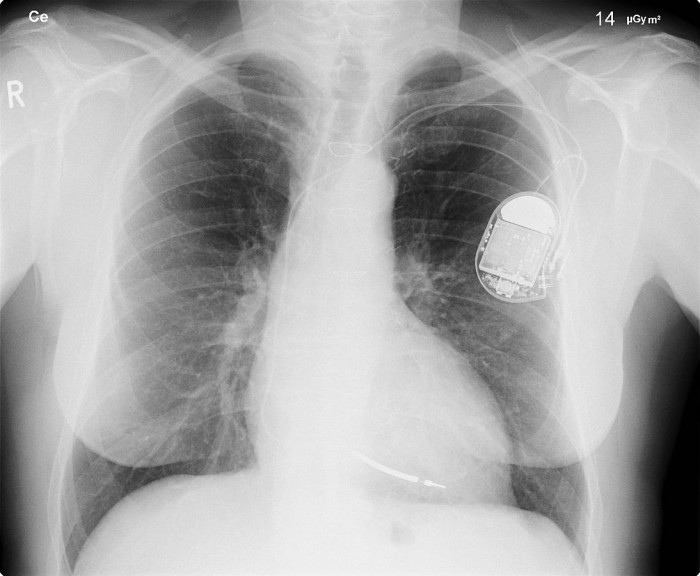

心脏起搏器

心脏起搏器最初并不是发明家Wilson Greatbatch所要创造的。根据康科迪亚大学的说法,心脏起搏器的概念自1932年起就已经存在。 然而,它们在当时还不太容易携带,是由一个手摇电机驱动的。不像我们今天的自动化机器那么方便。

直到1956年,作为工程师的Greatbatch在在研究一个记录人类心跳节奏的设备时,发生了一个非常幸运的意外。他在他的机器的电路中使用了错误大小的电阻,并意外地发现他的机器可以将电极直接运行到心脏的肌肉组织。随着时间的推移,这一意外发现最终导致了更小的起搏器,最终可以植入人们的身体--第一次成功的移植发生在1960年,使病人的生命延长了整整18个月。